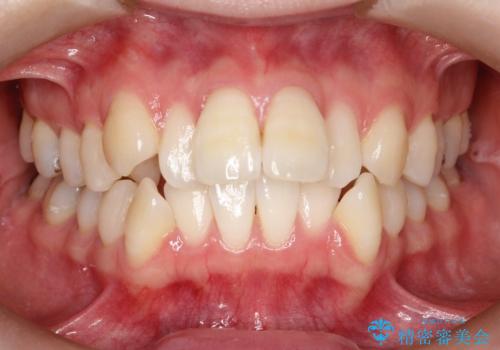

- 出っぱによる口元の閉じにくさを主訴に来院されました。上顎の出っ歯と上下顎叢生も認められたため、上下顎両側4番抜歯を行い、ワイヤー矯正で治療する治療計画を立てました。

少しスペースクローズに時間がかかりましたが、MIを用いたワイヤー矯正で

主訴である出っ歯と叢生が改善されました。口も閉じやすくなり、スッキリとした口元になりました。